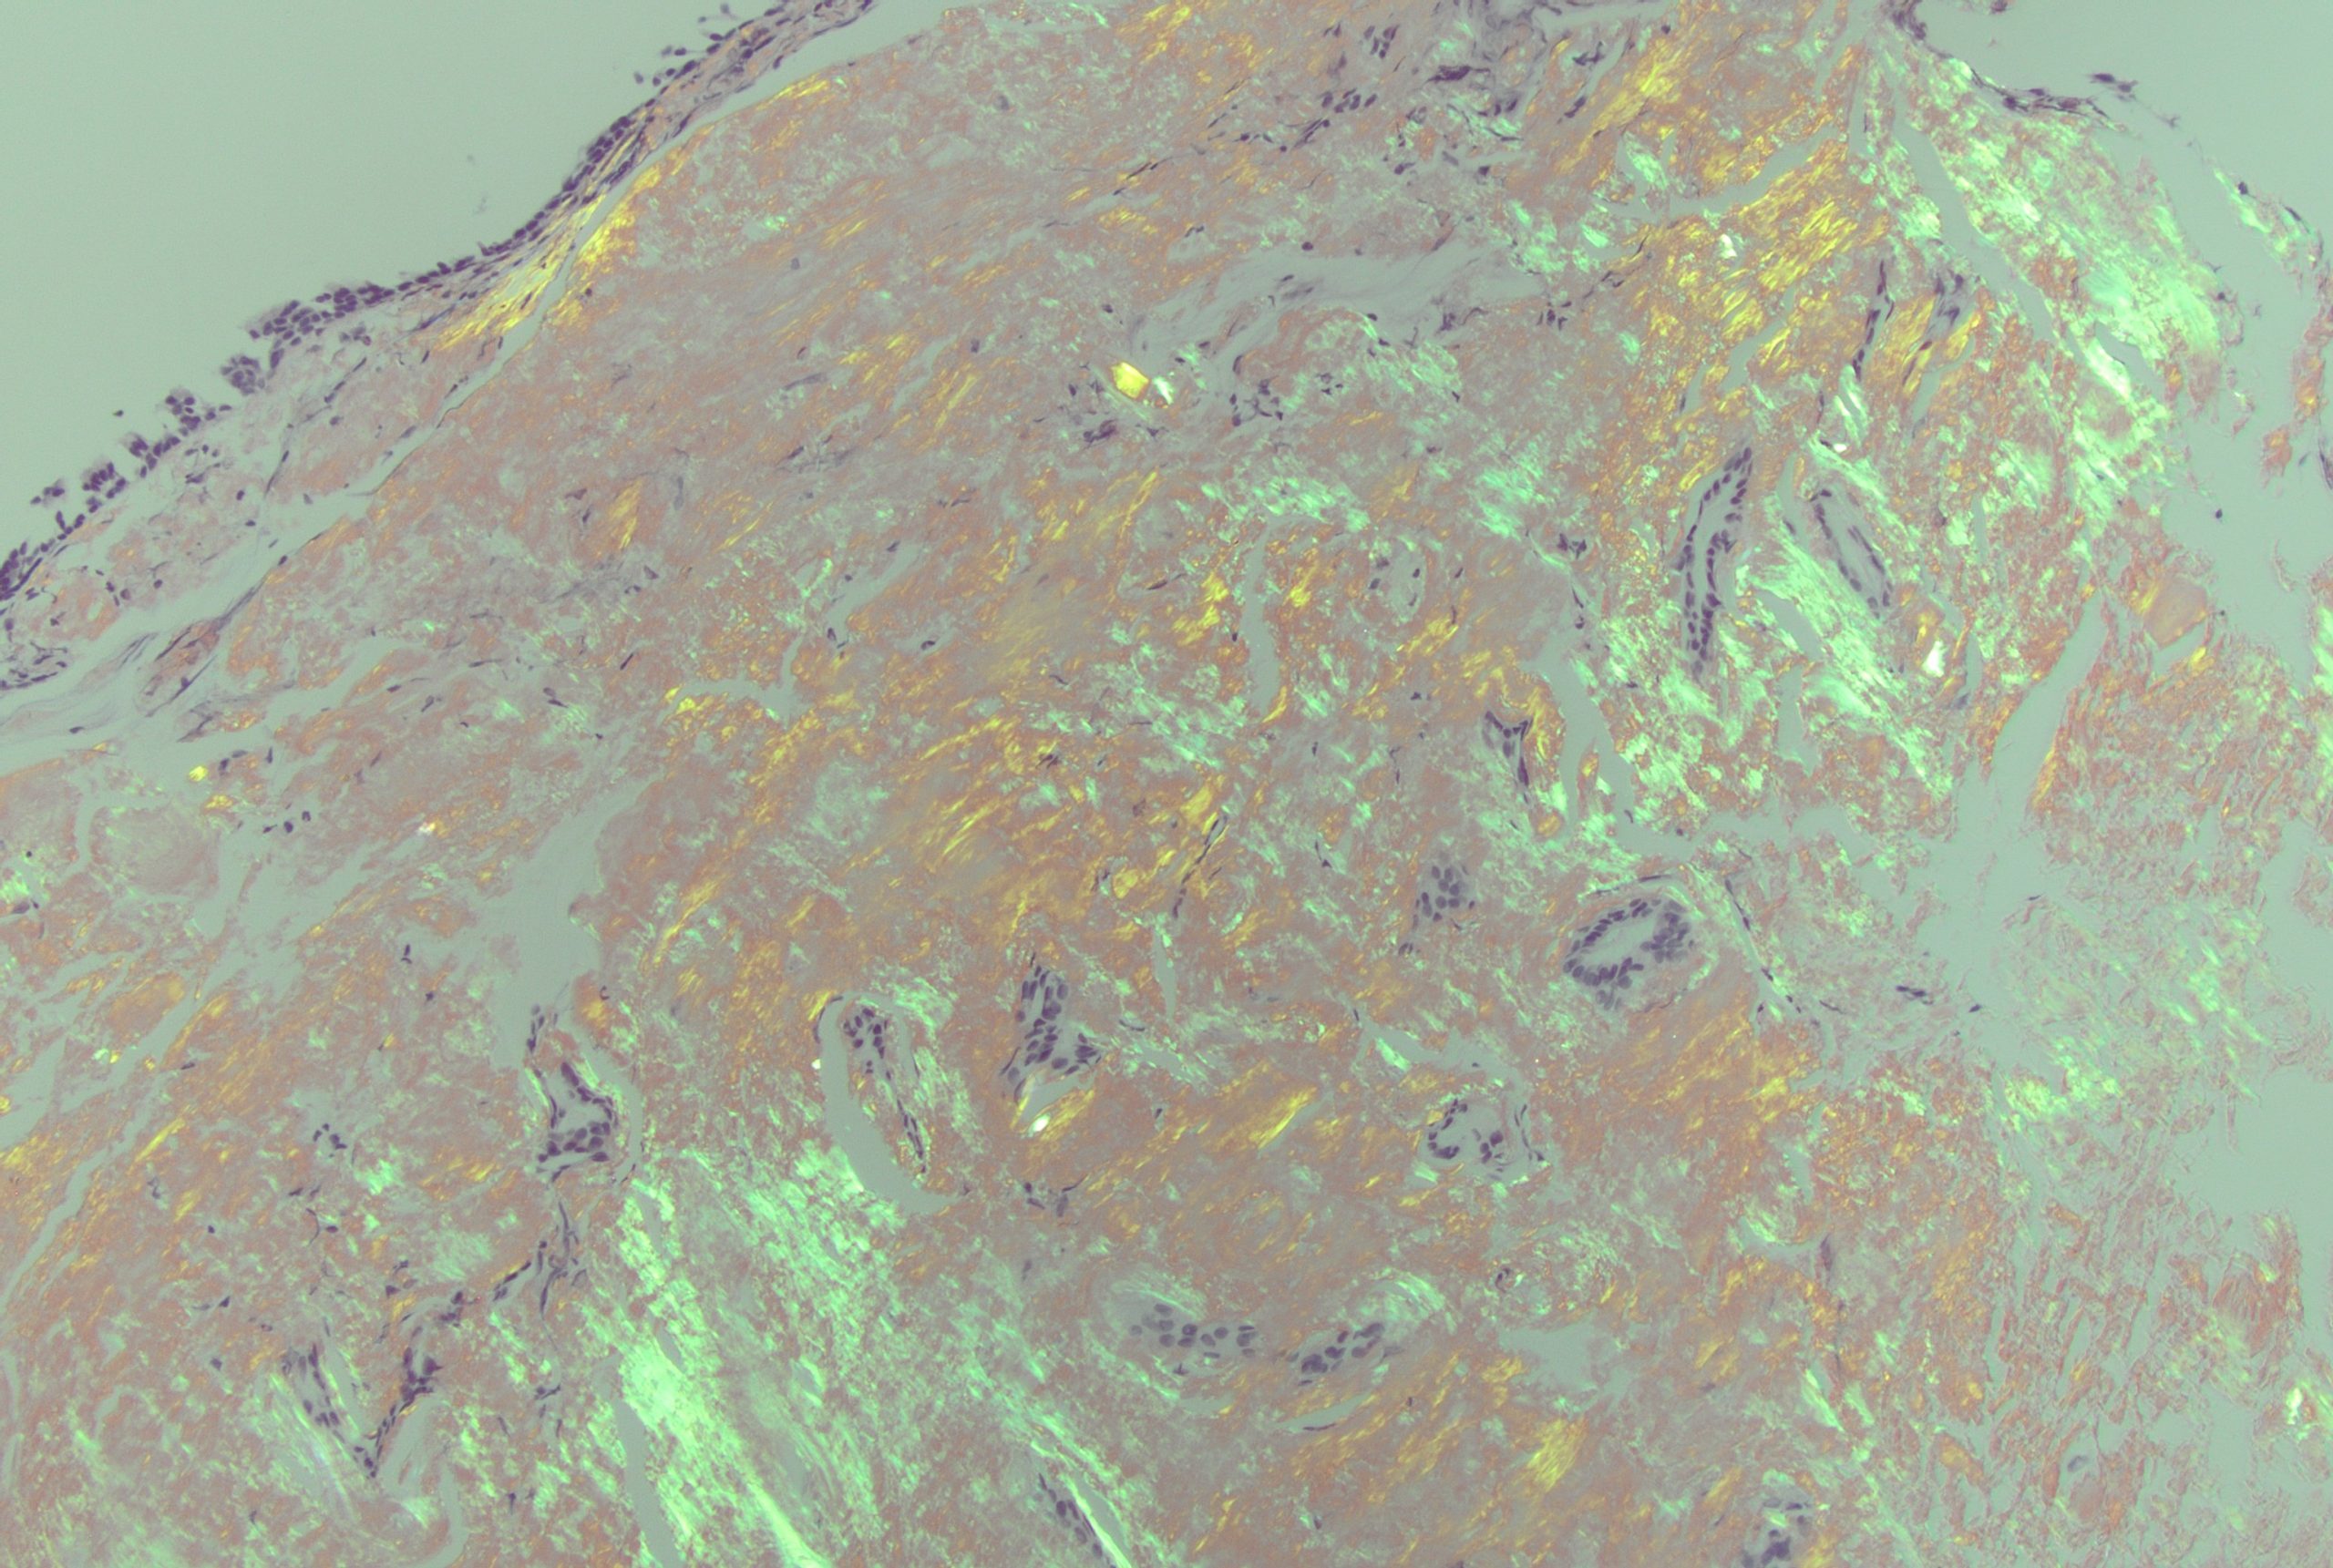

Case Presentation: An 81-year-old male with type 2 diabetes mellitus and emphysema visiting from Thailand presented to the Emergency Department for cough and shortness of breath over one week. Vitals included: 36.3C, 103/87 mmHg, 88 bpm. He was found to be hypoxic with an oxygen saturation of 69% on room air requiring non-invasive ventilation. Computed tomographic (CT) angiography of the chest was negative for acute pulmonary embolus, but notable for large circumferential mass encasing the trachea. Patient underwent bronchoscopy which showed an endobronchial circumferential tumor thickening causing a long stenotic segment at the mid-trachea. This was biopsied in addition to lymph node sampling. Patient underwent three endobronchial debulking and balloon dilation procedures on index admission. Biopsy confirmed diagnosis of AL amyloidosis via histopathology and Congo red staining. Cardiac magnetic resonance imaging (MRI) and CT of the abdomen and pelvis had no evidence of amyloid deposition. He was discharged on room air with outpatient follow-up. However, he presented again with worsening shortness of breath and was re-admitted. Patient was found to have an Aspergillosis tracheitis superinfection, where bronchial washings were positive for Aspergillus antigen as well as by PCR. He remains hospitalized for antifungal treatment and management of his tracheal mass including additional resection and radiation.